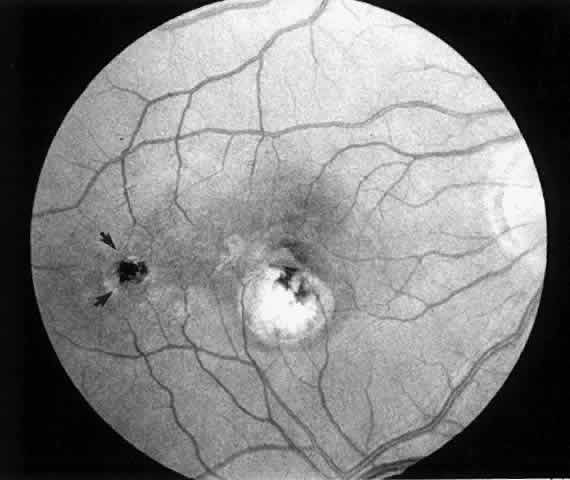

1. A 35-year-old patient with serpiginous choroidopathy developed a recurrent choroidal neovascular membrane extending into the fovea with a decrease in vision to 20/200 (6/60) (Fig. 7). Five months after surgery his visual acuity had improved to 20/25 (6/7.5) (Fig. 8).

2. A 35-year-old patient developed an idiopathic subfoveal choroidal neovascular membrane with decrease in vision to 20/200 (6/60) (Fig. 9). He underwent surgical excision of the membrane. Laser was applied to the retinotomy at the conclusion of the case. One year after surgery, his visual acuity remained stable at 20/20 (6/6) (Fig. 10).

Fig. 7. Preoperative fundus photograph of a 35-year-old patient with serpiginous choroidopathy and a recurrent subfoveal neovascular membrane (case 1). Visual acuity is 20/200 (6/60).

Fig. 8. Postoperative fundus photograph (case 1). Five months after surgery, patient's visual acuity is 20/25 (6/7.5).

Fig. 9. Preoperative fundus photograph of a 35-year-old patient with idiopathic subfoveal neovascularization (case 2). Visual acuity is 20/200 (6/60).

Fig. 10. Postoperative fundus photograph (case 2). One year after surgery, visual acuity is 20/20 (6/6). Note laser scar at retinotomy site (arrows).